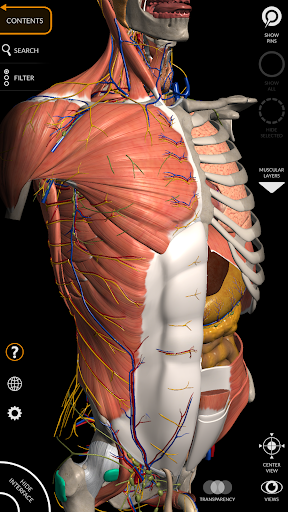

"Anatomy 3D Atlas" дозволяє легко та інтерактивно вивчати анатомію людини.

Завдяки простому та інтуїтивно зрозумілому інтерфейсу можна спостерігати кожну анатомічну структуру під будь-яким кутом.

Анатомічні 3D-моделі особливо деталізовані та мають текстури з роздільною здатністю до 4k.

АНАТОМІЧНІ 3D МОДЕЛІ

• Кістково-м’язова система

• Візуалізація м’язів через рівні шарів від поверхневих донизу до найглибших